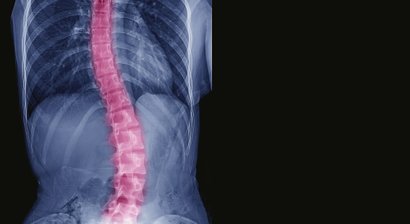

Skoliose

Bei einer Skoliose handelt es sich um eine Seitenabweichung der Wirbelsäule von der Längsachse, meist mit einer Rotation der Wirbelkörper – die Wirbelsäule wächst sozusagen in eine fehlerhafte Verdrehung hinein bzw. verkrümmt sich zur Seite.   Symptome Erkennen lassen kann sich eine Skoliose be...